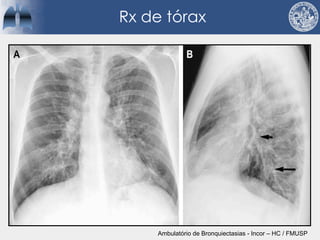

Rx de tórax

Ambulatório de Bronquiectasias - Incor – HC / FMUSP

Rx de tórax Ambulatóriode Bronquiectasias - Incor – HC / FMUSP